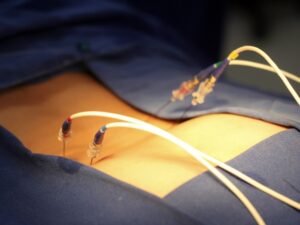

A neuroestimulação medular é um procedimento médico cirúrgico, no qual um dispositivo é implantado para fornecer estímulos elétricos controlados na

A discectomia e a descompressão percutânea são procedimentos cirúrgicos com técnicas minimamente e percutânea realizados para tratar a dor causada

A denervação das facetas por radiofrequência, também conhecida como rizotomia facetária por radiofrequência, é um procedimento médico minimamente invasivo utilizado

A rizotomia e a neurotomia por radiofrequência são procedimentos médicos minimamente invasivos realizados para tratar a dor crônica que não